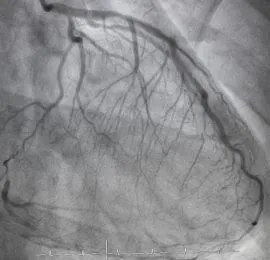

Angiography

Imaging test using contrast dye and X-rays to view blood flow in arteries and detect blockages.